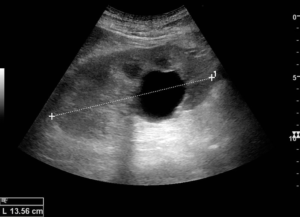

Обычно исследование начинают с проведения рентгена и скрининга. Также делается КТ (компьютерная томография) и пункционная кистография. Чтобы поставить диагноз и назначить эффективное лечение пациенту, применяется УЗИ.

При этом обязательно указывают расположение кисты паренхимы: левой или правой почки. Стадия патологического процесса определяется при помощи ультразвука и проведения МРТ, чтобы выявить такие патологии, как злокачественная киста паренхимы.

Обследование проводят, начав в рентгена с контрастным веществом, скрининга, используют компьютерную томографию. УЗИ-диагностику применяют для постановки диагноза, назначения эффективного лечения.

Локализация образования играет роль: справа, слева располагается киста паренхимы. Степень проблемы — злокачественное образование — определяют ультразвуком, магнитно-резонансной томографией.

При появлении симптомов болезни рекомендуется пройти ультразвуковое обследование, компьютерную или магнитно-резонансную томографию. Лечение назначается с учетом результатов обследования.

Пациентам рекомендовано провести ультразвуковое исследование почек, с помощью которого определяется месторасположение, параметры и структура новообразования. Пациентам назначают компьютерную и магнитно-резонансную томографию. С помощью КТ и МРТ уточняется информация, полученная при ультразвуковом исследовании.